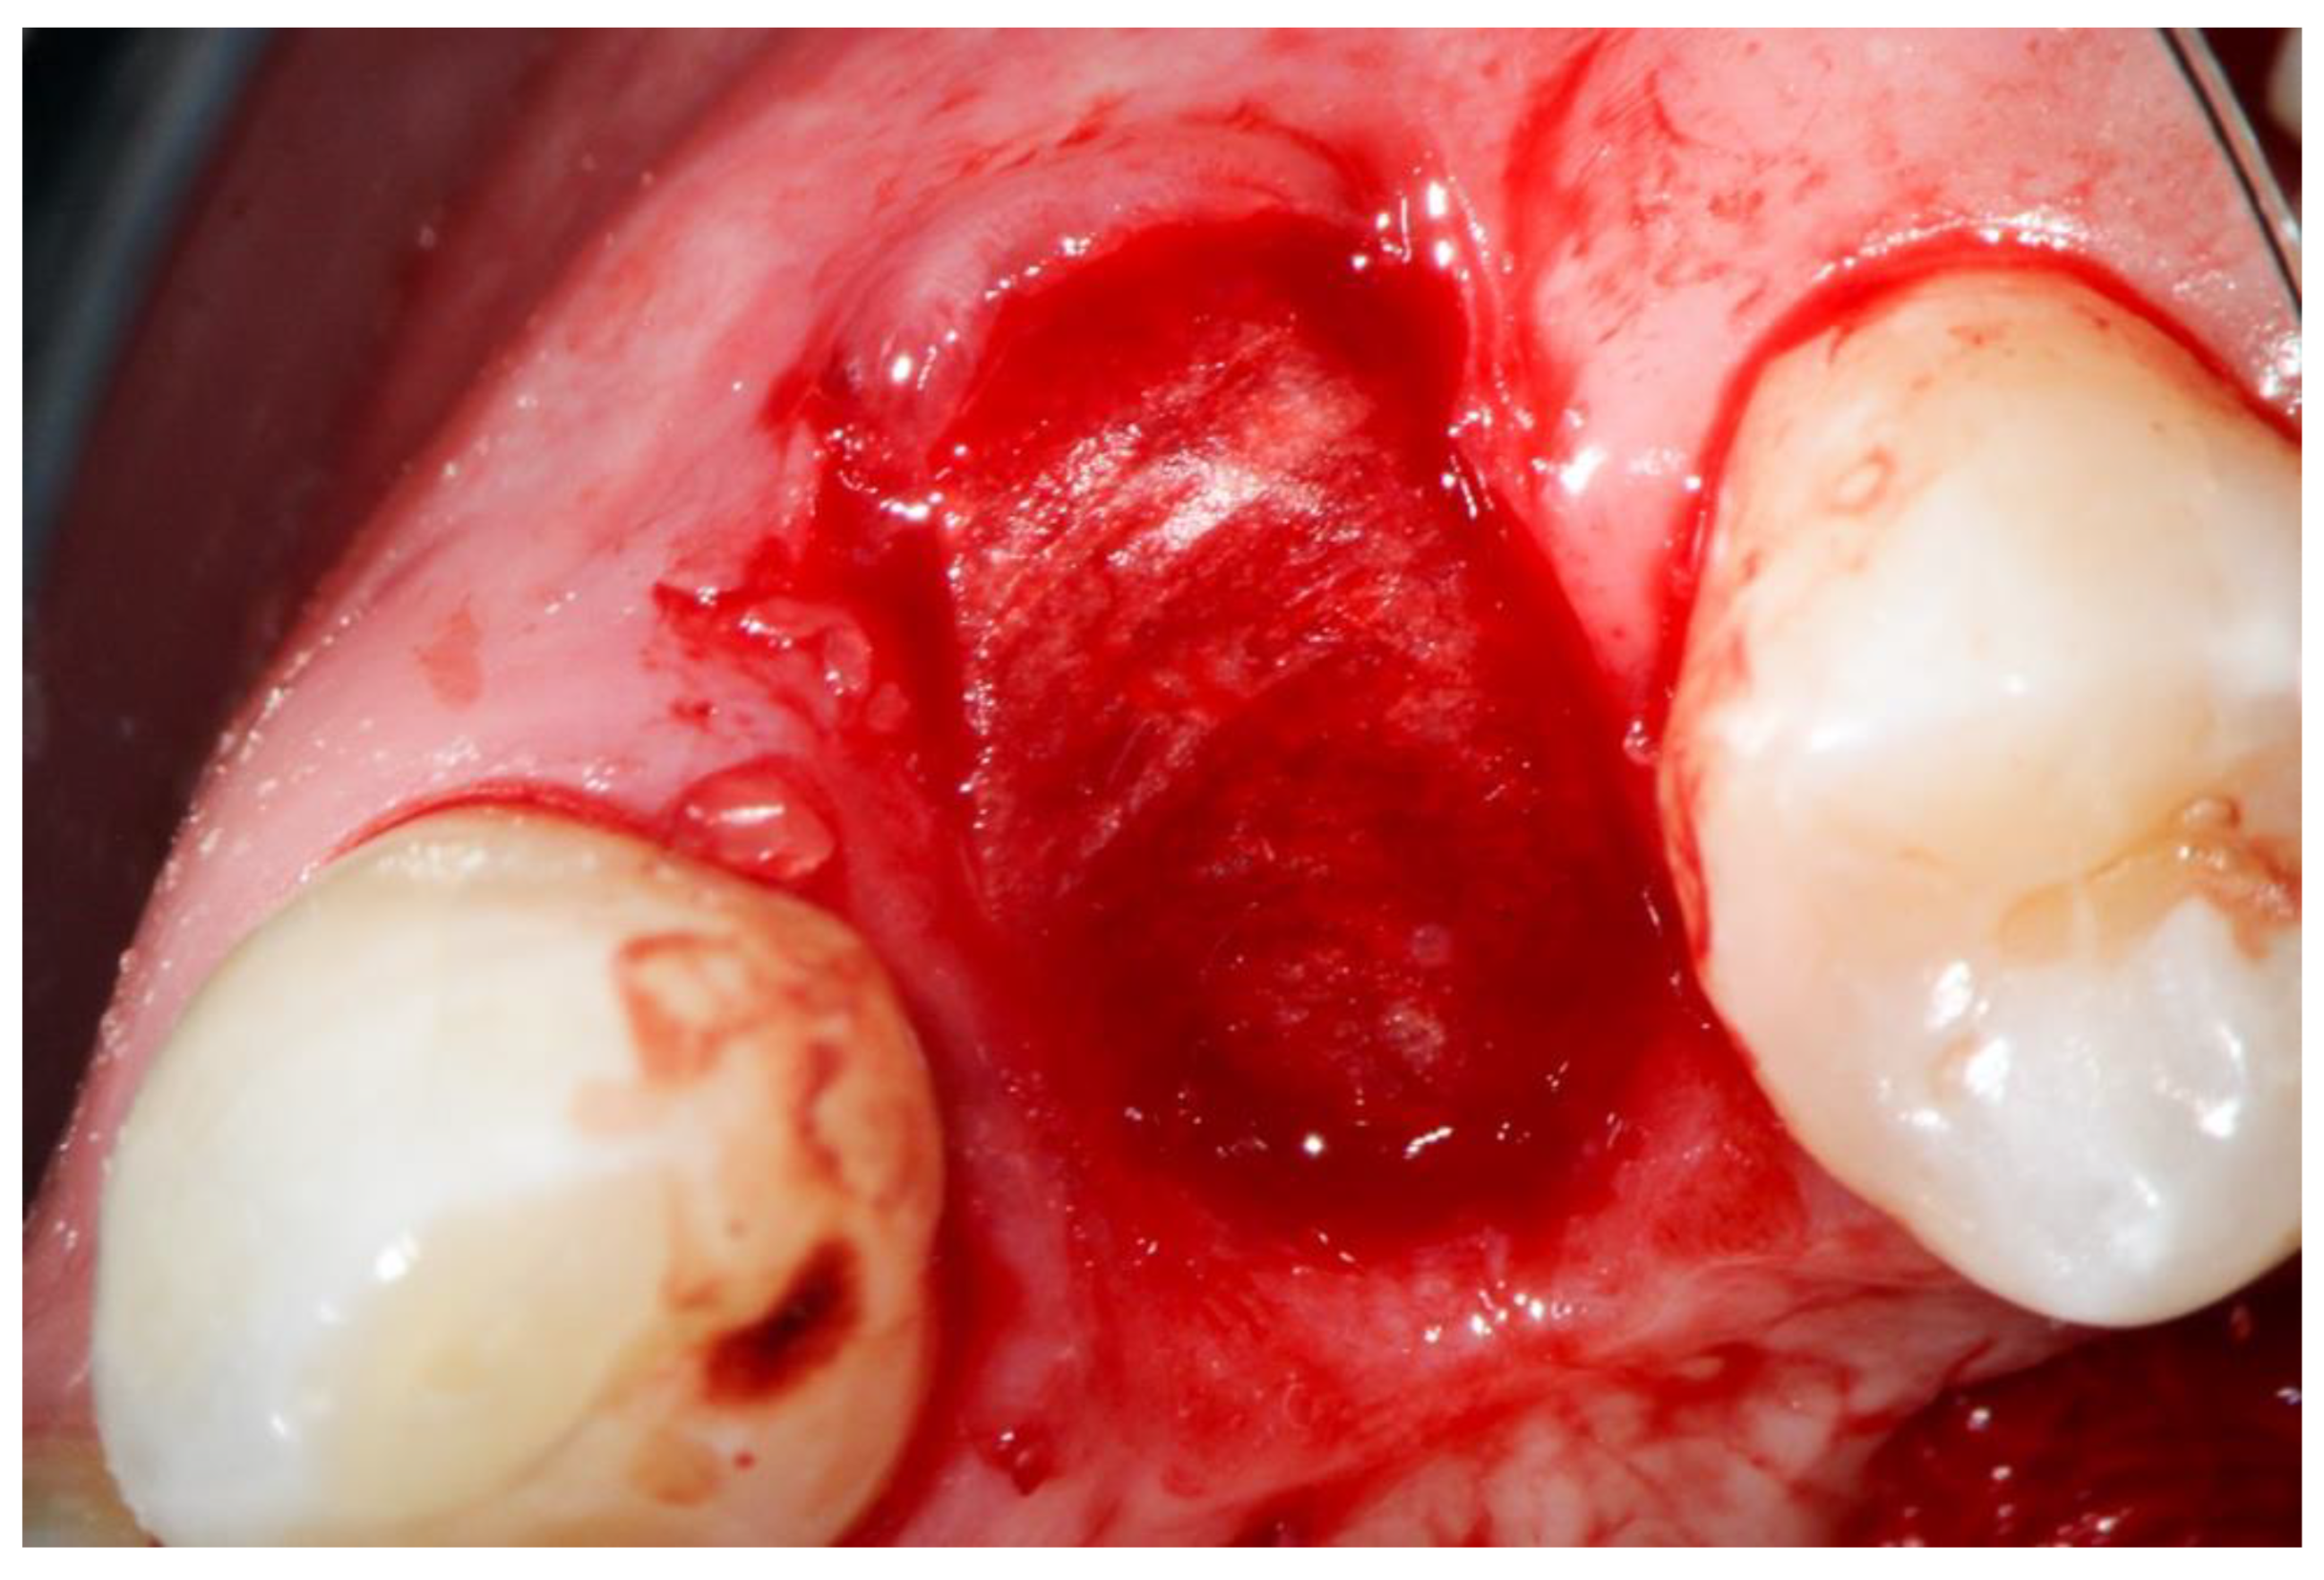

2. Materials and Methods